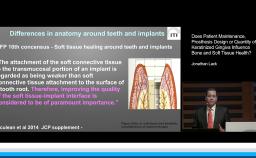

This lecture focuses on general aspects related to risk factors known to be associated with biological complications: both those that occur during the implant healing phase as well as those that occur after loading. Emphasis is on the prevalence of such complications and the role of periodontal disease, hardware problems, behavioral factors and medical conditions, which are presented through clinical cases.

- recognize different factors that play a role in implant complications during the healing phase and after functional loading

- recognize hardware-related factors that may play a role in implant complications